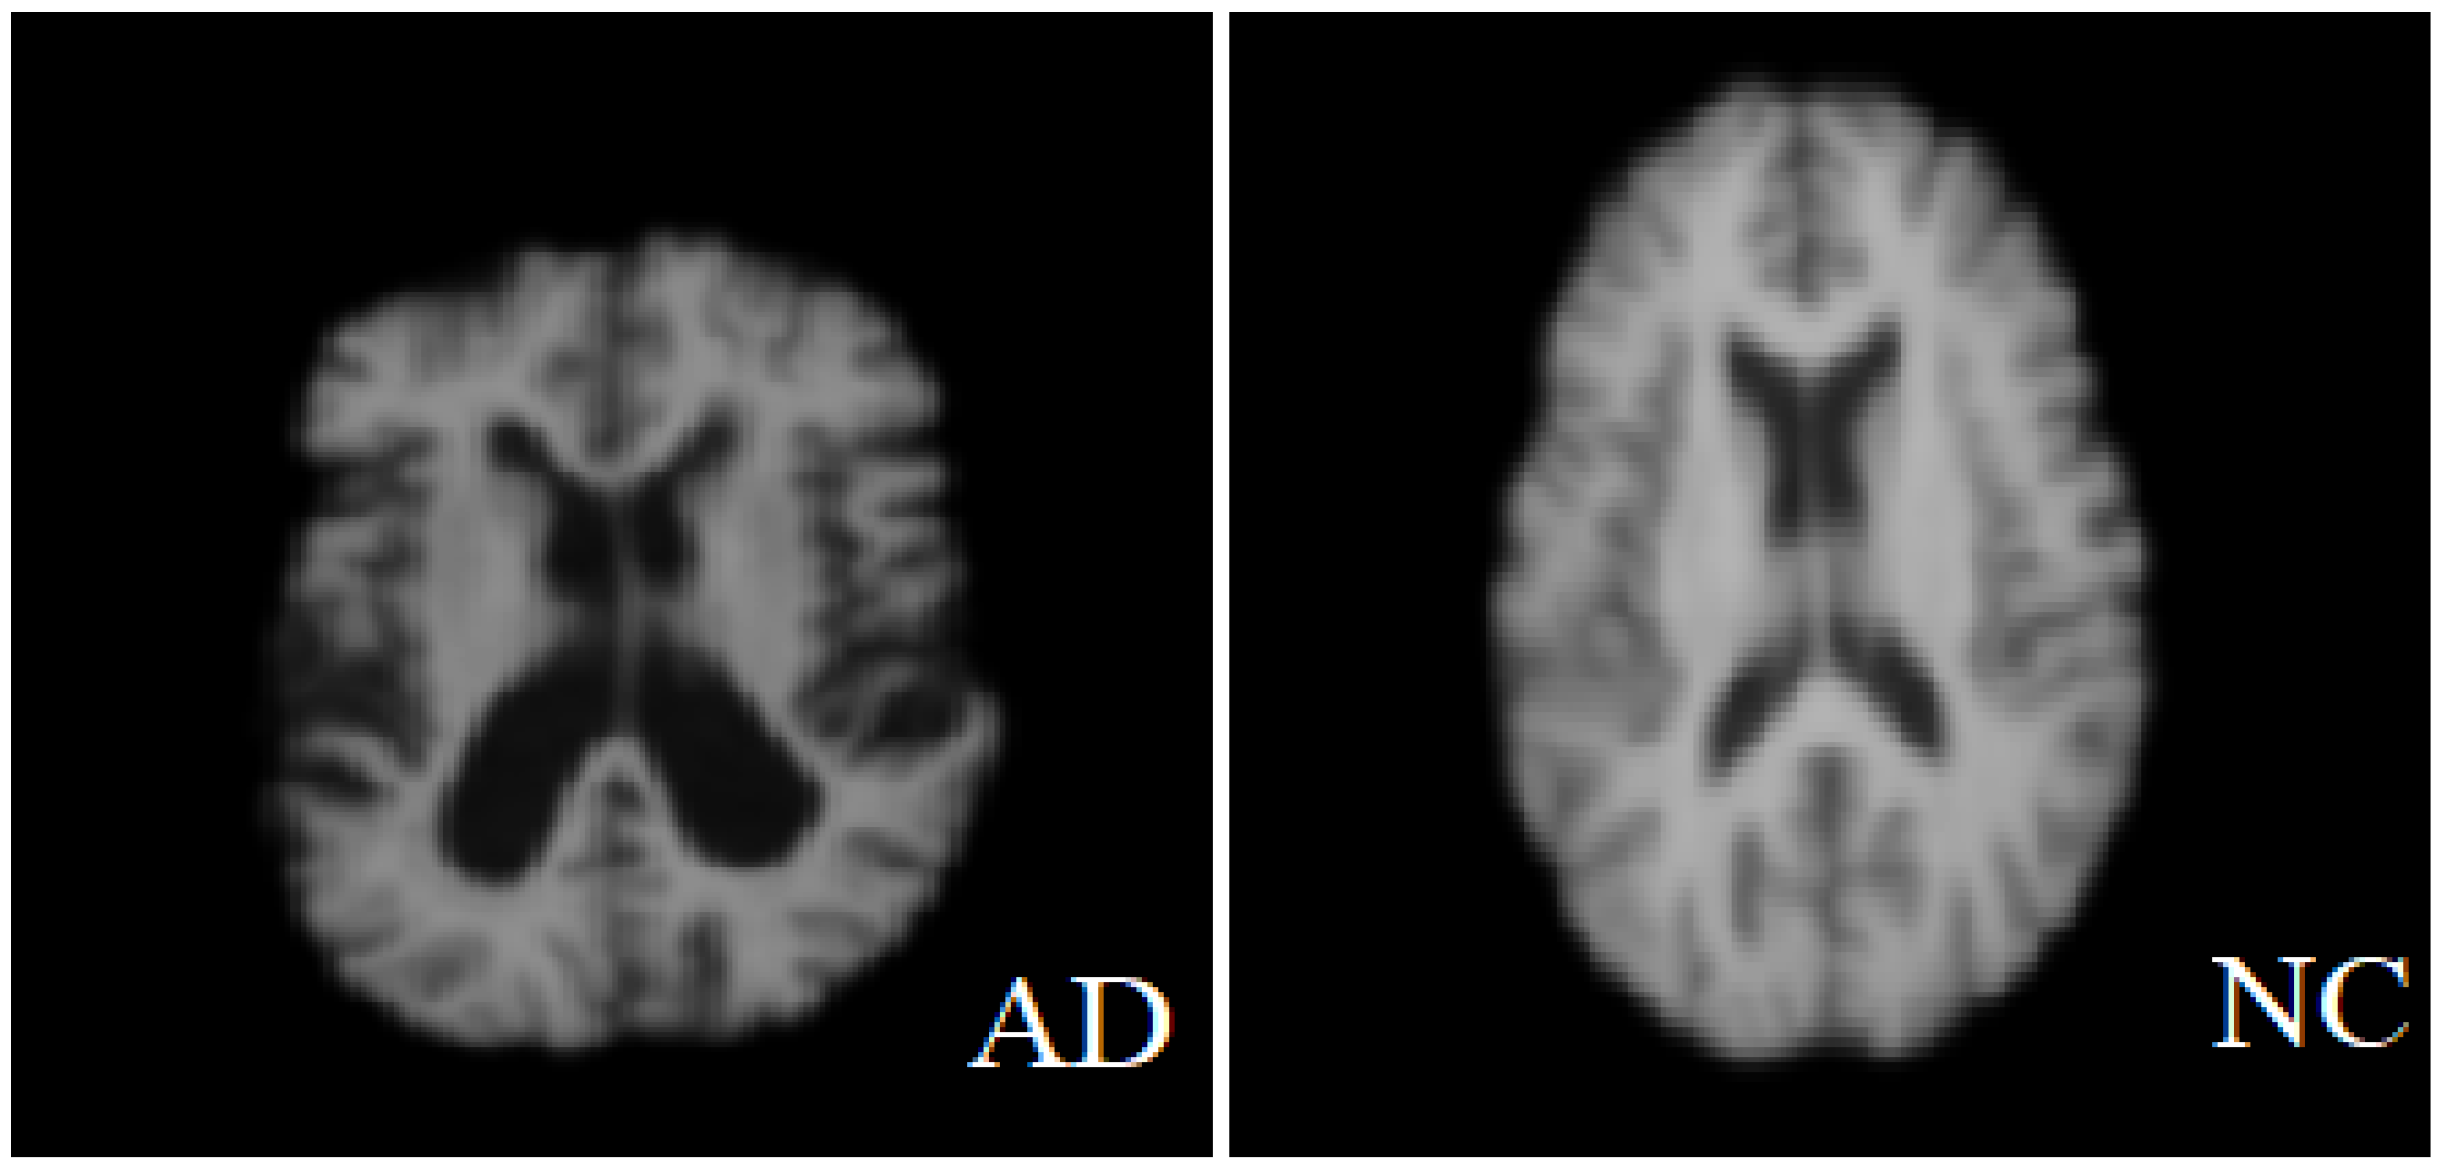

The data format is NIFTI and the file extension is (.nii). MRI data provide details of the brain and visualize the anatomy in all three planes: axial, sagittal, and coronal (see Figure 3 below). Figure 4 shows a comparison between a healthy brain (NC brain) and an AD brain of axial planes [18].

Figure 4.

Normal brain vs. brain affected with Alzheimer’s.